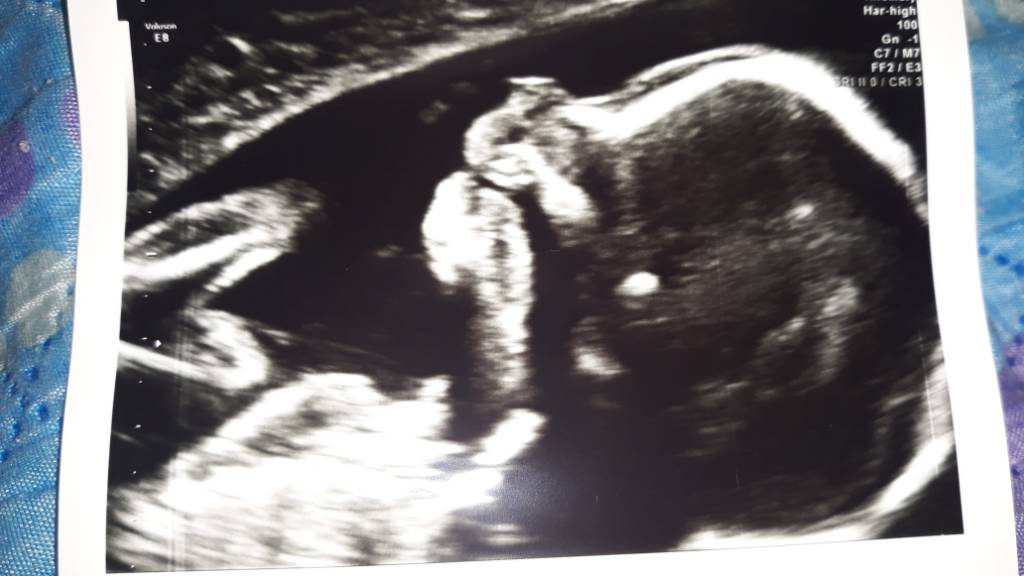

Witamy się! Już po połówkowych, 10 palców u rąk, nogi na miejscu, oczy, żołądek, śledziona i nerki na miejscu, serducho i płucka są. Dziąsła widziałam, zajęczej wargi nie ma, móżdżek się rozwija, kręgosłup też ok. Pępowina trójżylna, wody pod dostatkiem. Czyli wszystko tak jak ma być. Waga ok 290g. Matce już w bebechach grzebie. Chłop jak się patrzy!